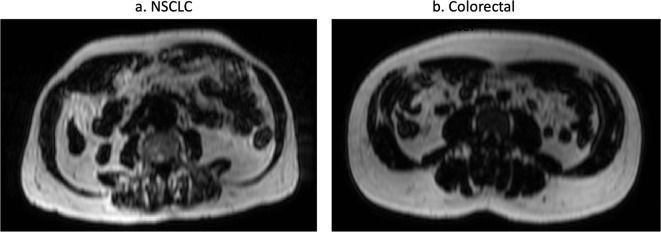

Objectives: To assess body composition in patients with non-small cell lung cancer (NSCLC) and colorectal cancer using whole-body MRI and relate this to clinical outcomes.

Methods: 53 patients with NSCLC (28 males, 25 females; mean age 66.9) and 74 patients with colorectal cancer (42 males, 32 females; mean age 62.9) underwent staging whole-body MRI scans, which were post-processed to derive fat mass (FM), fat free mass (FFM) and skeletal muscle (SM) indices and SM fat fraction (FF). These were compared between the two cancer cohorts using two-sided t-tests and the chi-squared test. Measurements of body composition were correlated with outcomes including length of hospital stay, metastatic status and mortality.

Results: Patients with NSCLC had significantly lower FFM (p = 0.0071) and SM (p = 0.0084) indices. Mean SM FF was greater in patients with NSCLC (p = 0.0124) and was associated with longer hospital stay (p = 0.035). There was no significant relationship between FM, FFM and SM indices and length of hospital stay, metastatic status or mortality.

Conclusions: Patients with NSCLC had lower FFM and SM indices than patients with colorectal cancer and greater SMFF, indicating lower SM mass with fatty infiltration. These findings reflect differences in the phenotype of the two groups and suggest patients with lung cancer are more likely to require additional nutritional support.

Advances in knowledge: Body composition differs between NSCLC and colorectal cancer. Patients with NSCLC have both a reduced SM mass and greater SM FF suggesting that they are more nutritionally deplete than patients with colorectal cancer.